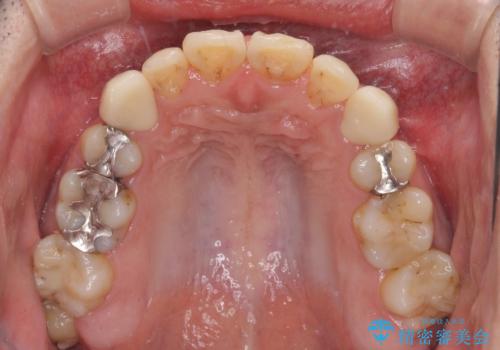

- 以前矯正を行った際に前歯が虫歯だらけとなり、審美面を気にして来院された患者様です。

虫歯の大きかった左右犬歯はオールセラミッククラウンで補綴治療をおこない、4前歯は研磨や古い充填物の詰め直しを行いました。

歯並びは良くなったものの、着色が気になって口元を見せることを躊躇していた用ですが、治療後は他人の視線を気にすることがなくなったようで、大変満足していただきました。